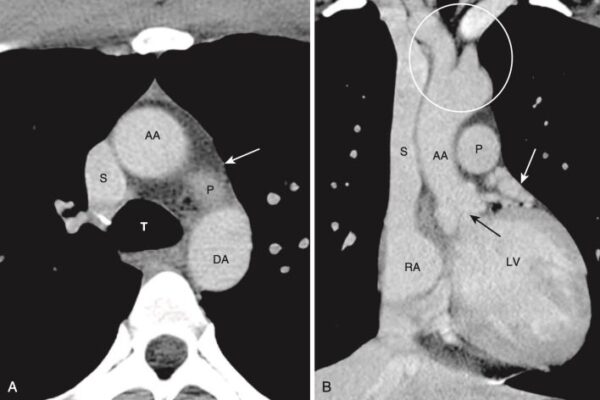

Hình 7. Mức cửa sổ chủ phế (A) và hình cắt đứng bên (vành/trán) (B). A, Ở mức này, có thể xác định được khí quản (T), động mạch chủ lên (AA) và động mạch chủ xuống (DA), tĩnh mạch chủ trên (S), và có thể là mặt trên của động mạch phổi trái (P), cửa sổ chủ phế (mũi tên trắng). B, CT đứng bên được định dạng lại cho phép chúng ta nhìn thấy cả tâm nhĩ phải (RA), tĩnh mạch chủ trên (S), tâm thất trái (LV), van động mạch chủ (mũi tên đen), động mạch chủ lên (AA), động mạch phổi chính (P), phần phụ tâm nhĩ trái (mũi tên màu trắng), và gốc của các mạch máu lớn (vòng tròn màu trắng).

Ở Mức động mạch phổi chính (Hình 8)

- Ở các mức này (có thể cần nhiều hơn một lát cắt để nhìn thấy tất cả các cấu trúc này), có thể xác định được động mạch phổi chính, động mạch phổi phải và trái; phế quản chính phải và trái; và phế quản trung gian.

- Động mạch phổi trái cao hơn bên phải và biểu hiện như thể là phần tiếp nối của động mạch phổi chính. Động mạch phổi phải xuất phát ở một góc 90° so với động mạch phổi chính và chạy chéo sang bên phải.

- Phế quản chính phải biểu hiện dưới dạng một cấu trúc hình tròn, chứa không khí, sau đó sẽ trở thành hình ống khi phế quản thùy trên bên phải xuất hiện. Sau phế quản trung gian không nên có gì ngoài mô phổi.

- Phế quản chính trái xuất hiện như một cấu trúc hình tròn chứa không khí ở bên trái.